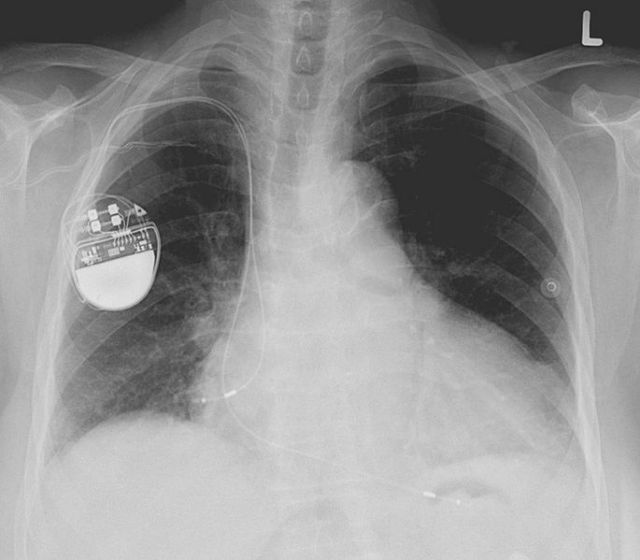

Όταν η κλασική νεκροψία αποτυγχάνει, οι βηματοδότες και άλλες εμφυτεύσιμες συσκευές που συνδέονται στην καρδιά είναι δυνατό να αποκαλύψουν τον χρόνο και την αιτία του θανάτου του κατόχου τους, διαπιστώνουν οι γιατροί.

Η ερευνητική ομάδα ανέλυσε στοιχεία για πάνω από 5.000 νεκροψίες, από τις οποίες οι 150 αφορούσαν ανθρώπους που είχαν στην καρδιά τους κάποια συσκευή: οι περισσότεροι βηματοδότη (107) ή απινιδωτή (22).